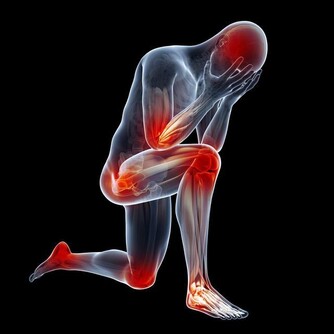

*****肢體症狀*****

腿抽筋大部分人的肌肉時不時地抽筋,這並無大礙。然而,如果你僅僅在散步時就經常感到大腿、臀部或小腿疼痛或抽筋,就要引起注意了。根據匹茲堡大學醫學中心心髒病專家的說法,這可能是主髂動脈閉塞性疾病的一個跡象。

手臂或肩膀疼痛如果這種疼痛在用力時持續出現,休息時感覺稍好,可能意味著心臟病正在醞釀。然而,如果你突然感到手臂、背部或肩部劇烈疼痛,加上胸部有擠壓感,很有可能是心髒病發作。

掉腿毛對於一些人來說,腿上沒毛既方便又美觀,但它可能是外周動脈疾病的一個跡象,這種循環病是指斑塊在動脈中積聚,並減少流向四肢的血液,這就會造成腿毛脫落。

腿發沉當你患有外周動脈疾病時,腿部血流量缺乏會使你走路時感到沉重不堪。它還會引起疼痛、抽筋、麻木或虛弱。

劇烈的背痛有時,心臟問題在身體意想不到的部位發出警告信號,其中一個就是背部。如果胸部的疼痛擴散到上背部或下背部,一定要及時就醫。根據克利夫蘭診所心髒病專家的說法,這可能是女性心臟病發作的一個微妙跡象。

腹痛如果你在運動時腹痛,但這種疼痛在休息後很快就消失了,那麼心臟可能在暗示你它正在發展為心臟病。

胸部不適胸部不適往往被人們忽視,認為這是吃了油膩的大餐造成的。然而,如果這種不適、擠壓、飽脹甚至輕微的疼痛發生在胸部中心,持續時間超過幾分鐘,這可能是心臟病即將發作的警告信號。